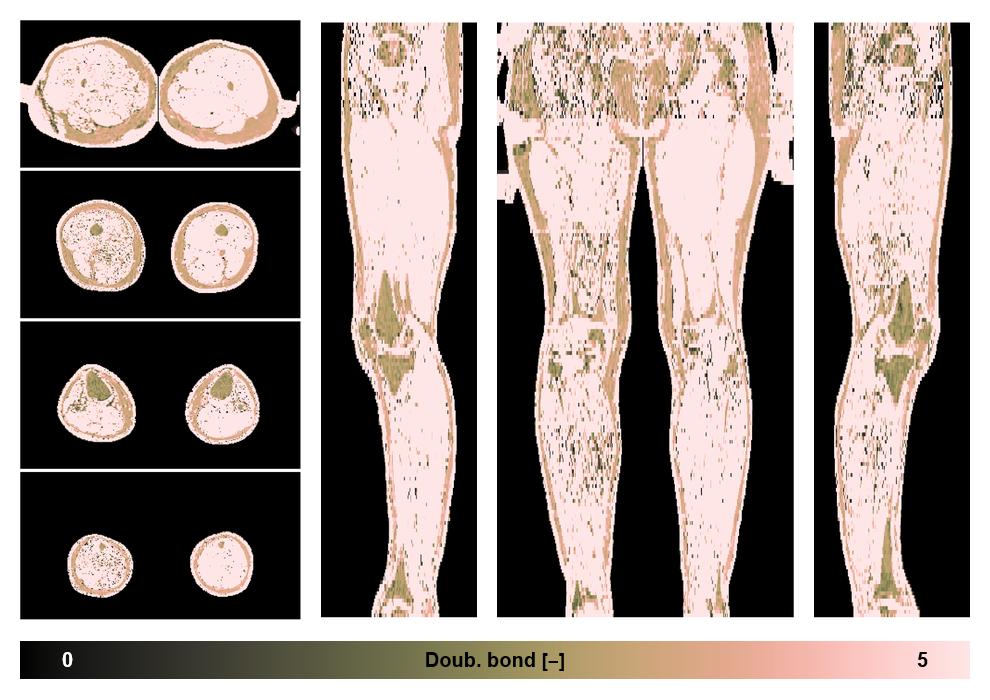

• Number of double bonds in subcutanious fat

Number of double bonds in subcutanious fat.